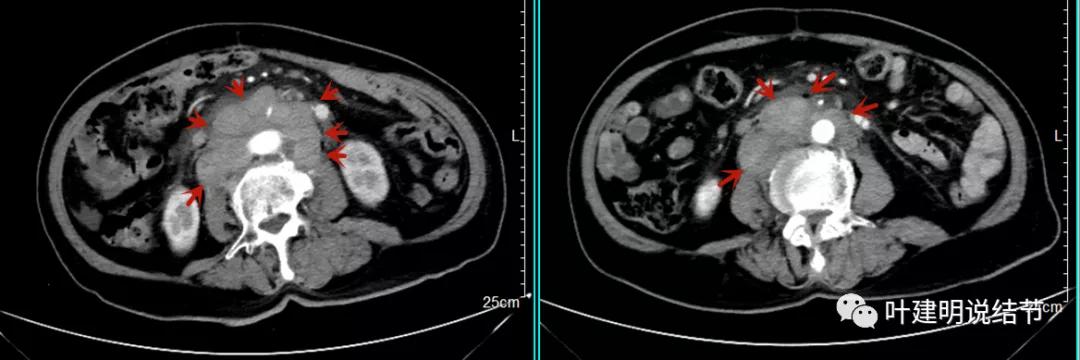

上图是初发现时的CT影像报告,其他CT图像上红色箭头所指范围内都是肿瘤,整合成团,挤压血管以及正常器官结构。你有见过原发灶这么不显眼,而腹部转移灶这么厉害的食管癌吗?但经过穿刺证实是转移性鳞癌,结合病史考虑是食管癌转移。手术自然是不可能了根治了,放疗也不合适,经过MDT并与患方充分沟通,依据食管癌治疗指南:

我们选择了“特瑞普利单抗加多西他赛加卡铂”的化疗加免疫治疗方案。我们来看经过一个周期治疗后肿瘤改善情况的对比: